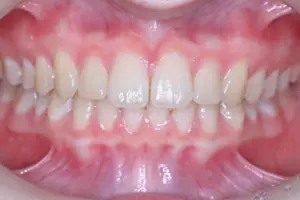

大人の矯正

「誰もが本当に喜べる矯正を提供したい」という治療目標を掲げる当院では、その実現のため、単に綺麗な歯並びに整えるだけでなく、原因の部分をきちんと治して、矯正後の咬み合わせの違和感や体調の変化を最小限に抑える治療を行なっています。

その結果として、治療期間の短縮や後戻り予防、たくさんの患者様からの喜びのお声につながっています。